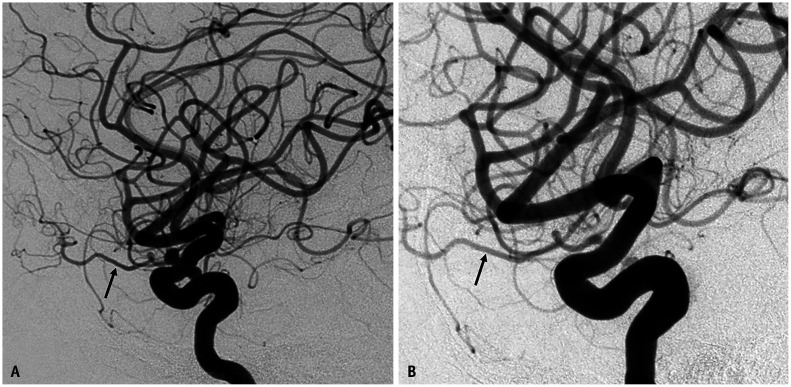

Abstract Image